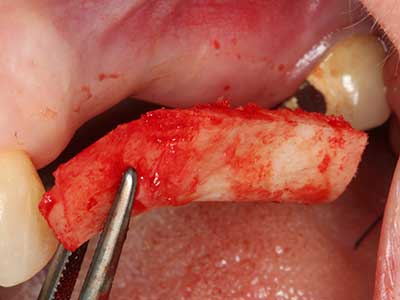

Autogene Knochentransplantate finden als Blöcke, Schalen, Ringe und gerade in der Kombination mit Knochenersatzmaterialien als Späne Anwendung. Wird gleichzeitig mit der Augmentation ein Implantatbett aufbereitet, so haben sich zur Sammlung der anfallenden Knochenspäne verschiedene Knochenfiltersysteme bewährt. Alternativ kann eine niedrigtourige Implantatbettpräparation ohne Wasserkühlung erfolgen. Wird kein Implantat inseriert, so lassen sich mit Bone Scrapern Knochenspäne aus der Peripherie gewinnen. Ebensolches ist auch mit speziellen Ansätzen mittels Piezochirurgie möglich, wobei sich in einer eigenen Studie im direkten Vergleich zu mit Rosenbohrern gewonnenen Spänen eine bessere Qualität für die Piezospäne nachweisen ließ (Chiriac, Herten et al. 2005).

Bei der Knochenblockentnahme zeigen sich weitere Vorteile für die Piezochirurgie: Neben der bereits beschriebenen hohen Präzision bei der Osteotomie stellt sich gerade die Verwendung der dünnen Sägespitzen als besonders materialschonend heraus. Bei der Verwendung insbesondere von Lindemannfräsen sind mit deutlich höheren Entnahmeverlusten durch die dickere Instrumentenspitze zu rechnen (Lakshmiganthan, Gokulanathan et al. 2012). Die insbesondere bei retromolar entnommenen Blocktransplantaten notwendige basale Abtrennung wird durch speziell hierfür vorgesehene rechtwinklige Sägen erleichtert, so dass die Piezochirurgie als präzises, übersichtliches und sicheres Verfahren zur retromolaren Knochenblockgewinnung angesehen wird (Happe 2007) (Abb. 1-12).